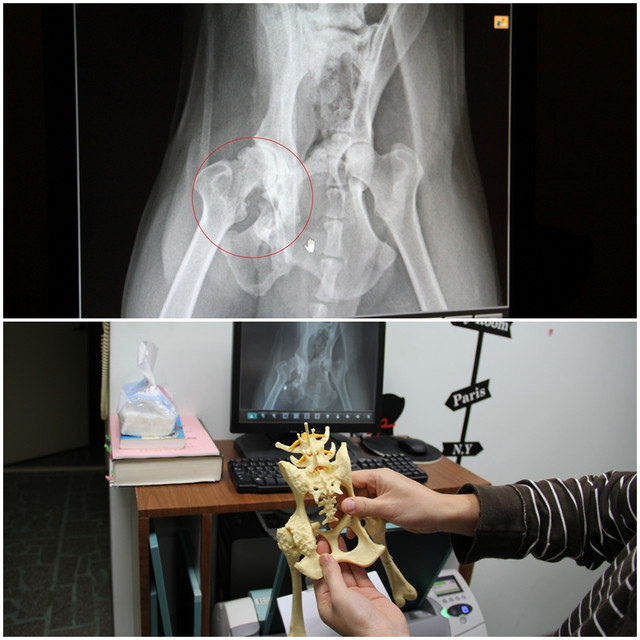

邱醫師拿了一個模型跟我解說,

你可以看到他左手指頭的位置,有兩個圓圓的洞,這就是閉瑣孔。

對照上方小黑的X光片,小黑的右邊骨盆的閉鎖孔已經消失了,這代表小黑右邊的整個骨盆曾遭受過外力的撞擊而粉碎。

現在自體的癒合讓他的骨盆自行黏合成為一整陀骨頭,造成他現在的身體上下左右都成為一個S型。這也是運氣不錯,骨盆狀況更糟的,不僅無法站立,行走,甚至連排便都會有問題。

邱醫師的建議是先為小黑做右腳髖關節手術,左腳應該可以先不要動,至於骨盆傾斜的問題,因為已經癒合了,也就沒有辦法治療了。